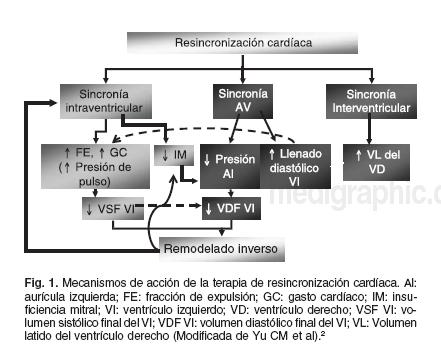

El bloqueo completo de la rama izquierda del Haz de His (BCRIHH) produce los efectos1,2 que se mencionan en la

Figura 1 (modificada de los trabajos de Yu et al): el propio BCRIHH produce una disincronía o asincronía de la contracción del ventrículo izquierdo, esto tiene como consecuencia por un lado disminución de la contractilidad cardíaca (+ dp/dT) que puede llegar a producir reducción de la fracción de expulsión, con o sin un descenso del gasto cardíaco y, en consecuencia un eventual empeoramiento de la situación hemodinámica y de la clase funcional del paciente. Por otra parte, esta asincronía intraventricular favorece y aumenta la presencia de regurgitación mitral diastólica o presistólica, debida a la contracción retardada de los músculos papilares y la contracción tardía de la pared lateral. La segunda consecuencia de la alteración de la conducción cardíaca es la disincronía auriculoventricular, que condiciona una menor aportación de la contribución auricular al llenado ventricular, con lo que aumenta la presión de la aurícula izquierda y el volumen diastólico final del ventrículo izquierdo. El propio retardo de la sístole conduce a una reducción del tiempo de llenado que a su vez empeora el patrón de llenado ventricular o condiciona la aparición de disfunción diastólica. Finalmente, también se produce una disincronía interventricular, que disminuye el volumen sistólico del ventrículo derecho y por tanto el del ventrículo izquierdo. Por tanto, la alteración eléctrica que se produce en el BCRIHH tiene una serie de consecuencias mecánicas y hemodinámicas que, en última instancia, producen un proceso de remodelación ventricular patológico.

Mecanismos de acción propuestos de la terapia de resincronización cardíaca

Se han propuesto diversos mecanismos de acción de la resincronización cardíaca.5 Uno de ellos es el incremento del tiempo de llenado ventricular izquierdo. En presencia de BCRIHH, la activación ventricular se retrasa, pero no la auricular. Por eso, tanto el llenado ventricular pasivo como el activo de la contracción auricular se producen simultáneamente (fusión de la onda E y A), ocasionando una reducción del flujo sanguíneo transmitral total y una disminución de la precarga. La estimulación precoz del ventrículo izquierdo le permite iniciar la contracción antes, lo que aumenta el período de llenado. El segundo mecanismo es la reducción de la discinesia septal con un desajuste cronológico, ya que el septum se aleja de la pared ventricular durante la sístole y deja de contribuir al vaciado ventricular. Por lo que reduce la aportación del septum al gasto sistólico del ventrículo izquierdo. Otro mecanismo propuesto es la reducción de la regurgitación mitral diastólica. La regurgitación mitral diastólica es una consecuencia frecuente de la disincronía intraventricular, ya que la activación llega también retrasada al músculo papilar. La estimulación precoz del ventrículo izquierdo produce la activación anticipada del músculo papilar, con una reducción de la regurgitación mitral que ocurre fundamentalmente en la presístole.